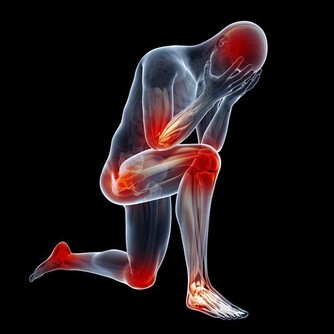

●肩膀痛嗎?擔心五十肩上身嗎?中醫師蔡曜鍵將教你一招「招財貓運 動」,讓五十肩退散!

●常常肩頸痠痛、還是落枕嗎?這招學起來超好用!中醫師蔡曜鍵現場 示範頸椎拿法。

●記下手腳各兩個穴位,搶救你的腰背痠痛,自行按壓或貼磁珠,自救 不求人

●膝蓋退化了沒!中醫師蔡曜鍵教你自行檢測,還要提供養膝茶飲!還 不快抄起來。